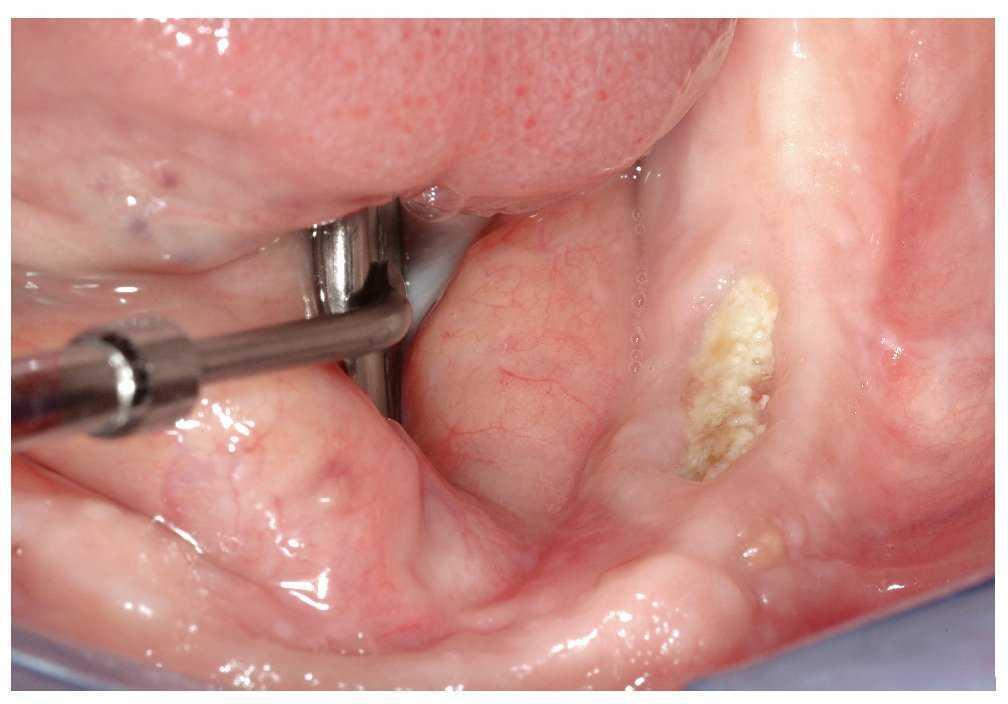

Figura 2b. En la primera exploración en julio de 2007 destacó la presencia de un secuestro óseo expuesto en la región 37 en vestibular. La región osteonecrótica era indolora y la única molestia que percibía el paciente se debía al borde óseo afilado.

Figura 3b. En la región 34 a 36 mandibular se observa una zona ósea superficial expuesta hacia vestibular. La paciente rara vez percibe dolor en la zona de la osteonecrosis, sólo ocasionalmente con el consumo de alimentos dulces o ácidos.

Figura 4b. Se observó una dehiscencia de tejidos blandos con exposición ósea superficial en el sector postero-inferior (región 34 a 36 hacia vestibular).